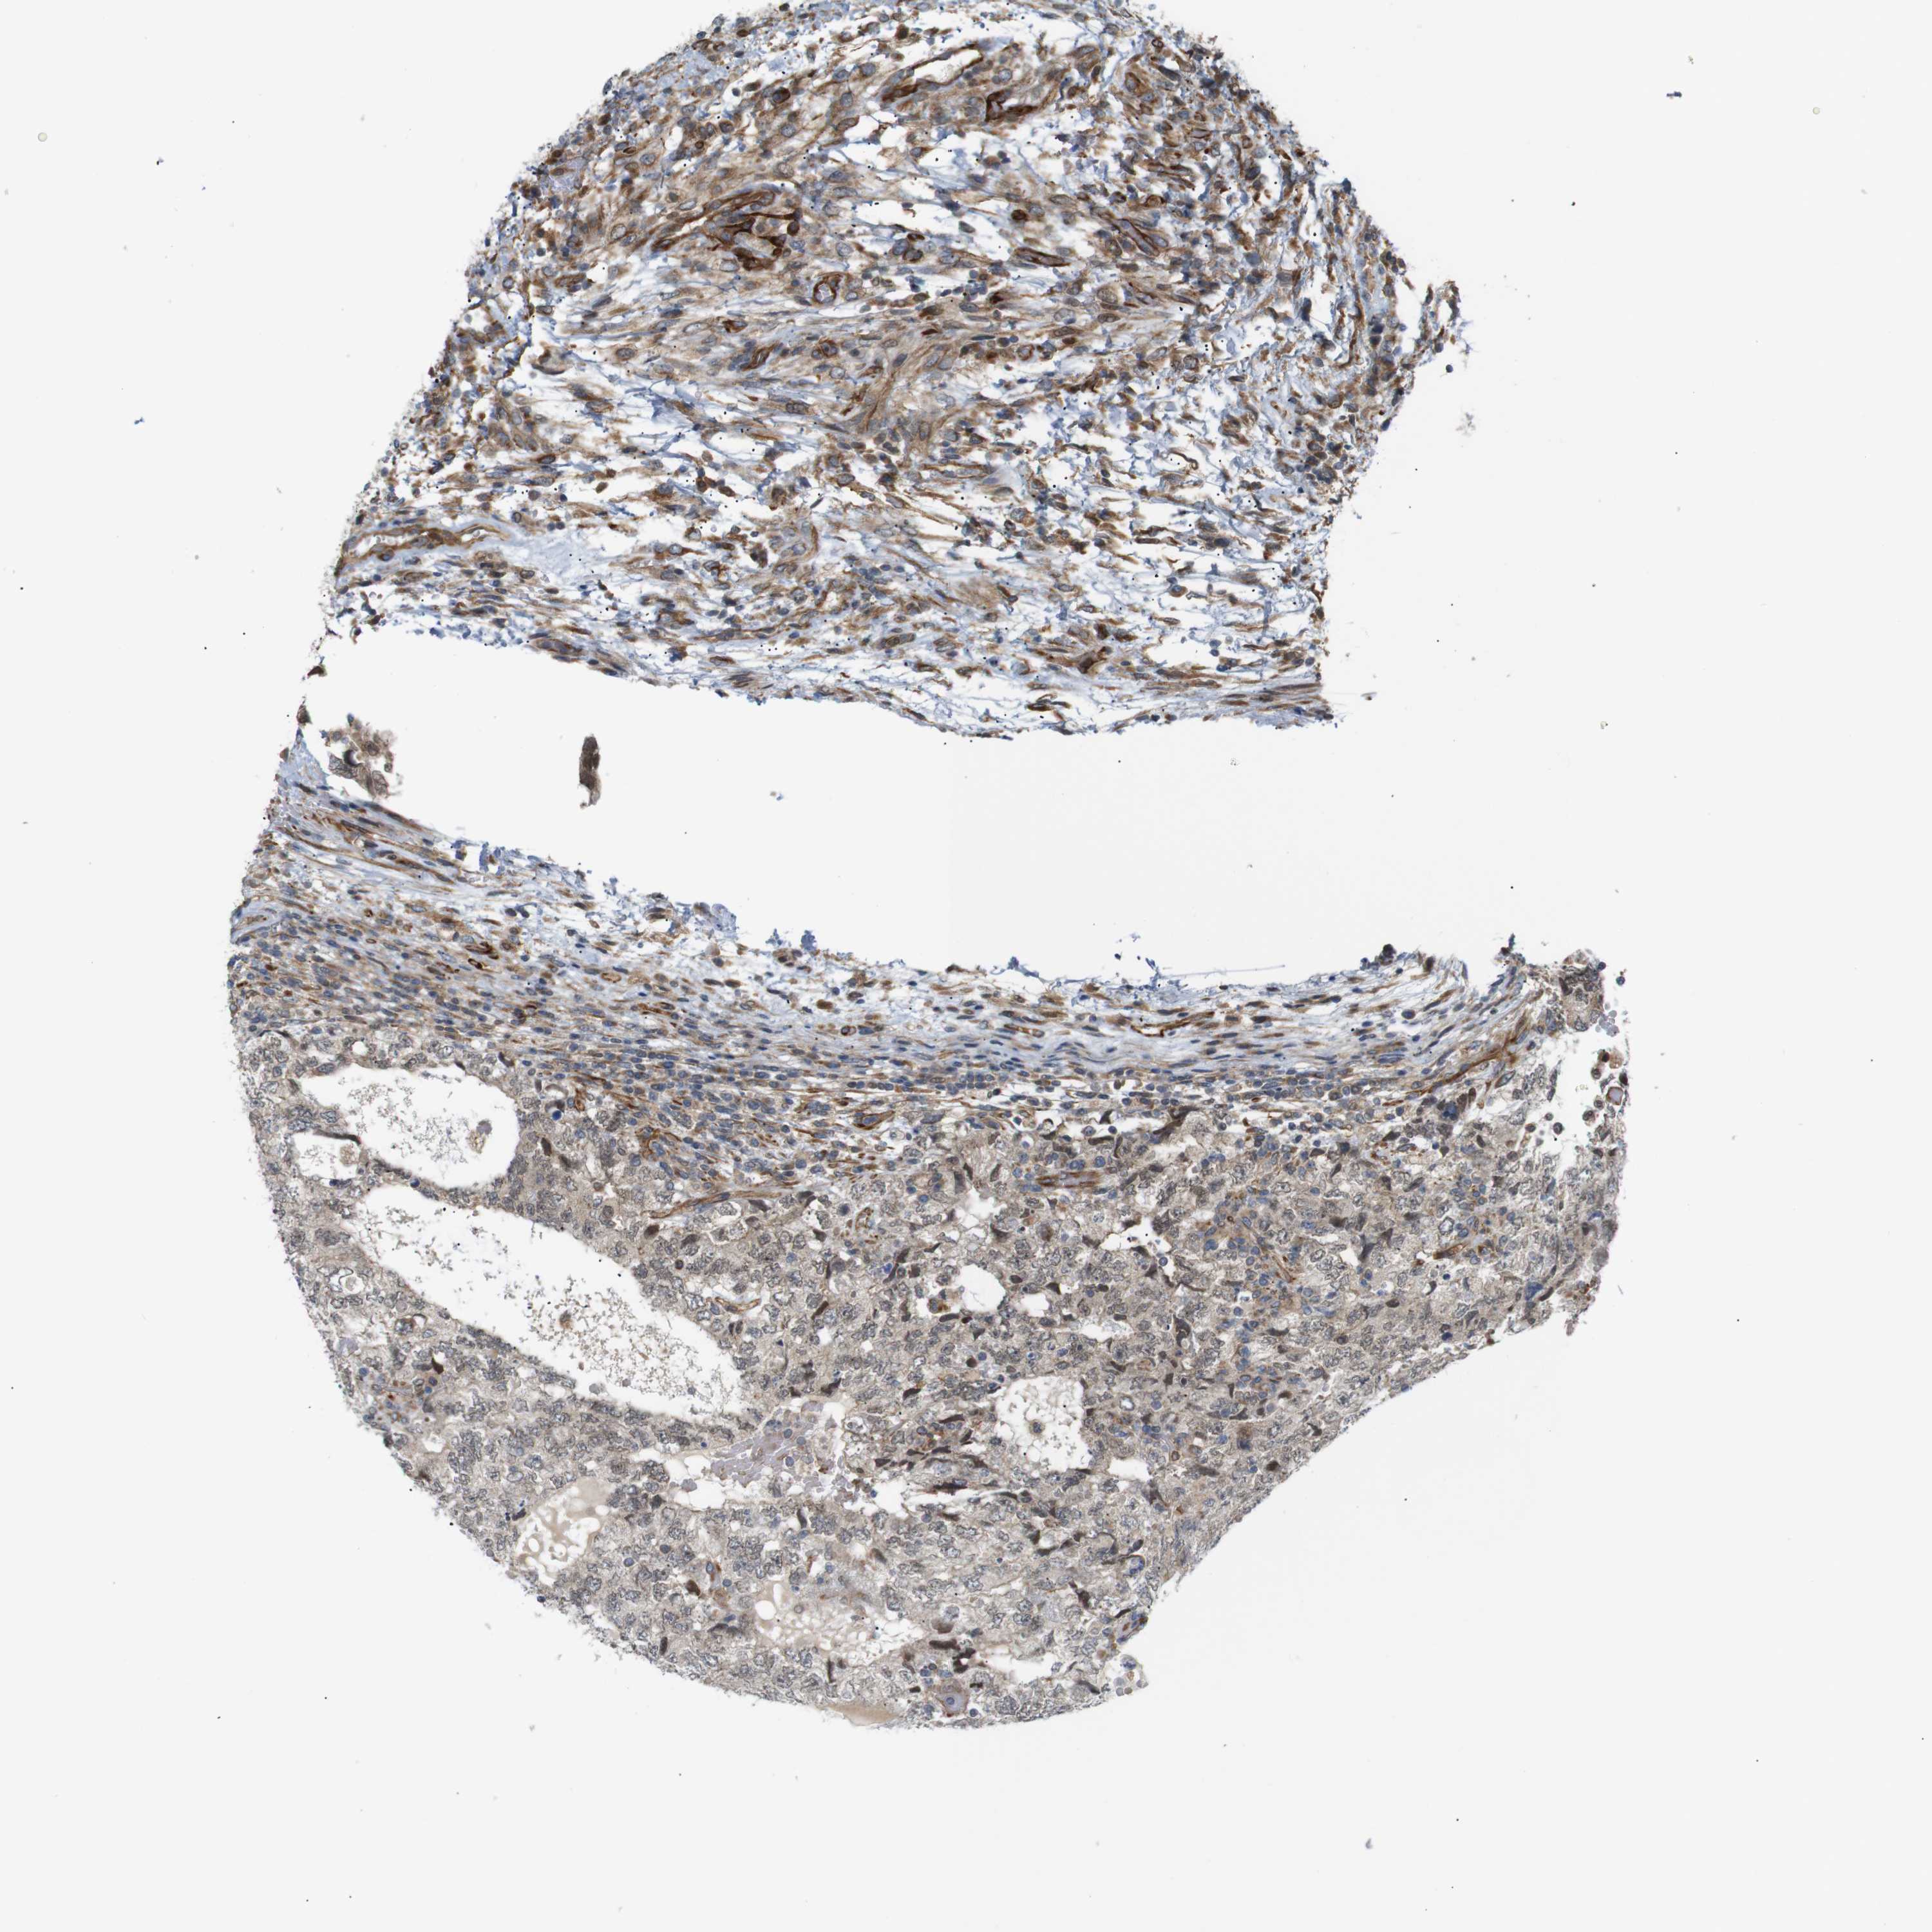

TESTIS CANCER - Protein expressioni

A mouse-over function shows sample information and annotation data. Click on an image to view it in a full screen mode. Samples can be filtered based on level of antibody staining by selecting one or several of the following categories: high, medium, low and not detected. The assay and annotation is described here.

Note that samples used for immunohistochemistry by the Human Protein Atlas do not correspond to samples in the TCGA dataset.

Antibody stainingi

Antibody staining in the annotated cell types in the current human tissue is reported as not detected, low, medium, or high, based on conventional immunohistochemistry profiling in selected tissues. This score is based on the combination of the staining intensity and fraction of stained cells.

Each image is clickable and will lead to virtual microscopy that enables deeper exploration of all samples and also displays staining intensity scores, fraction scores and subcellular localization as well as patient and tissue information for each sample.

Antibody CAB013514

Staining

High

Medium

Low

Not detected

Intensity

Strong

Moderate

Weak

Negative

Quantity

>75%

75%-25%

<25%

None

Location

Nuclear

Cytoplasmic/membranous

Cytoplasmic/membranous,nuclear

Carcinoma, Embryonal, NOS

Seminoma, NOS